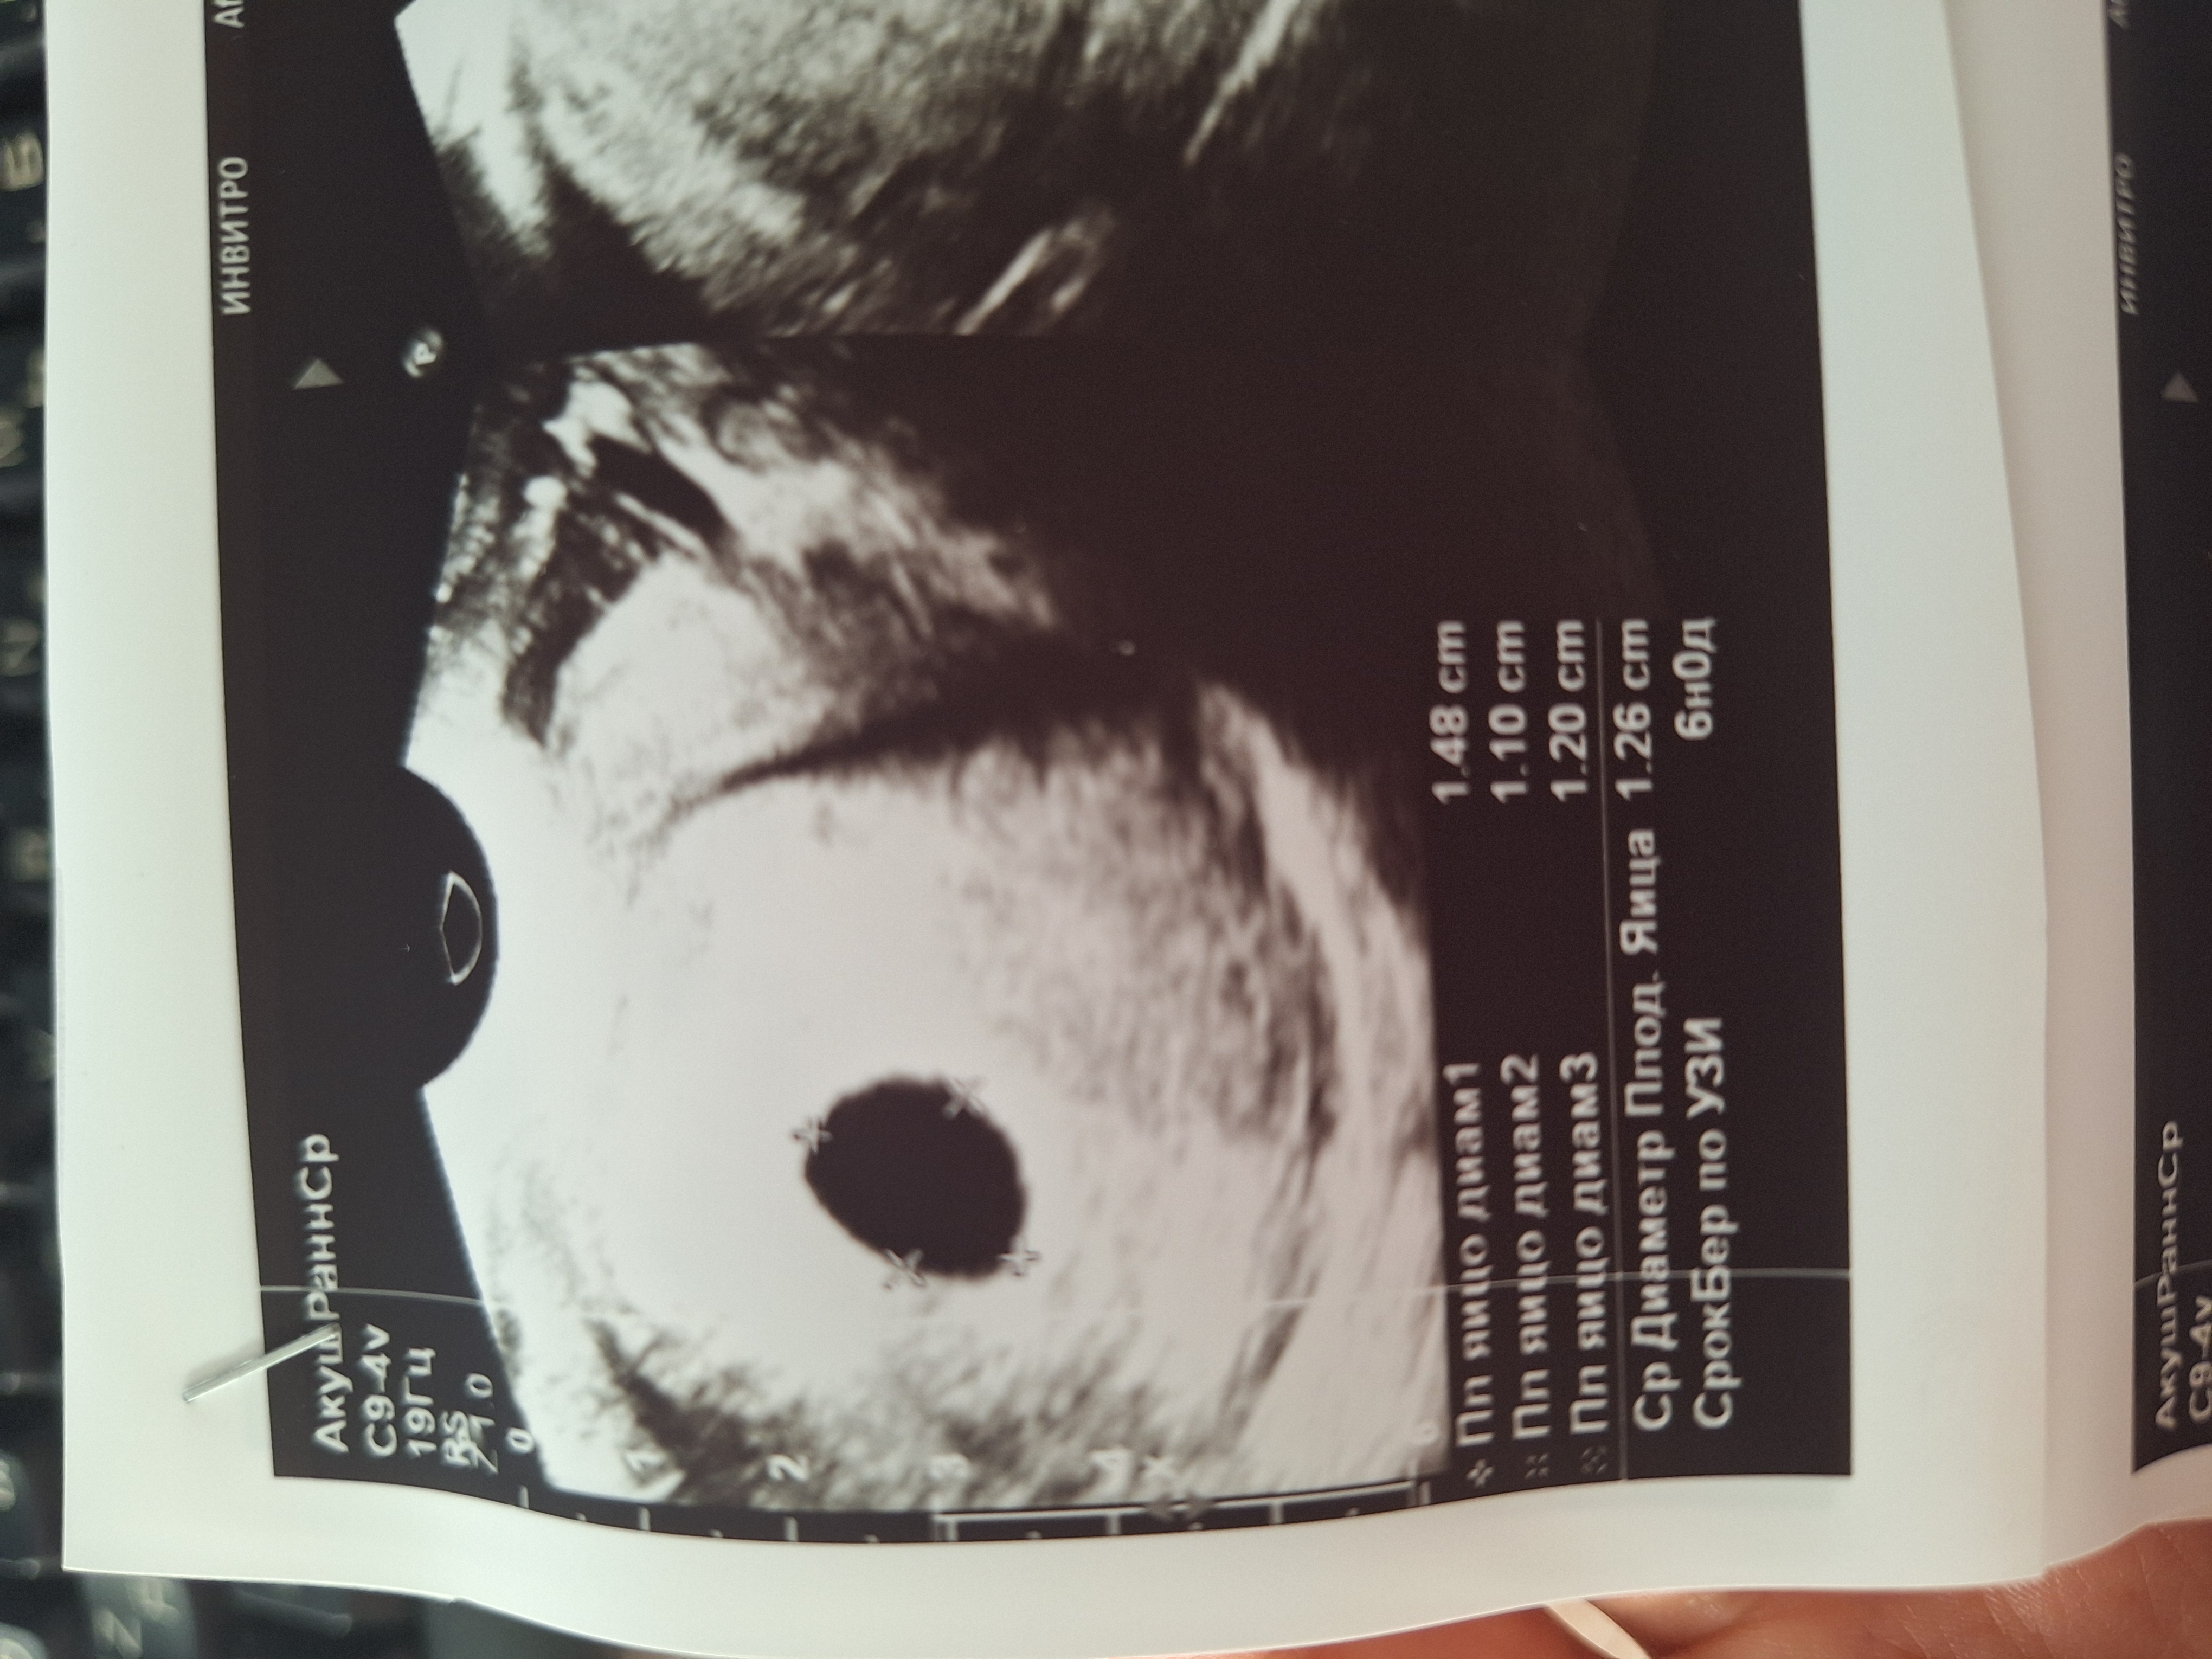

Little Koldynia, яйцо на 6 недель Изображение

Аня, плодное размер от роста хгч зависит иногда и 6 недель оно 6 мм. А иногда и 26мм.